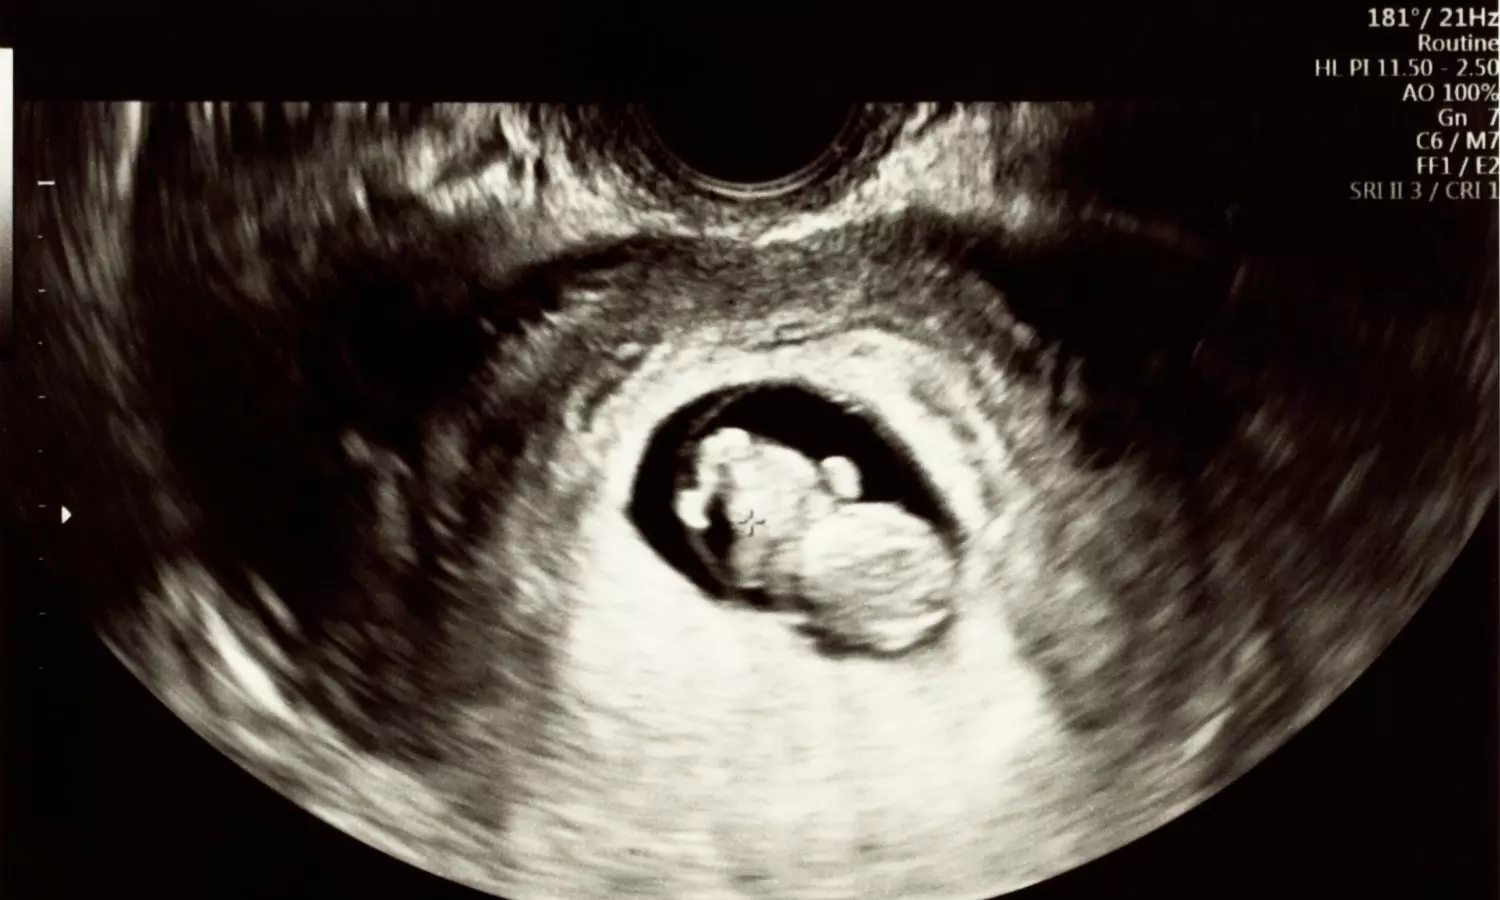

Recent research suggests that the use of antibiotics during pregnancy may increase the risk of newborns developing Group B Streptococcus (GBS) disease, a common but potentially serious bacterial infection. GBS bacteria are usually harmless and commonly found in the gut or genital tract of healthy adults. However, in vulnerable groups such as newborn babies, older adults, and people with weakened immune systems, the infection can lead to severe complications.

In newborns, GBS infection can cause life-threatening conditions, including sepsis, meningitis, and pneumonia, particularly in the first few weeks after birth. The latest study highlights a possible link between prenatal antibiotic exposure and a higher risk of GBS disease in infants.

The research was conducted by an international team of scientists from the Karolinska Institutet in Sweden and the University of Antwerp in Belgium. The researchers found that babies exposed to antibiotics before birth were more likely to develop GBS disease within four weeks after delivery. The risk was especially high when antibiotic exposure occurred during the early third trimester, which appears to be a critical period for newborn susceptibility.